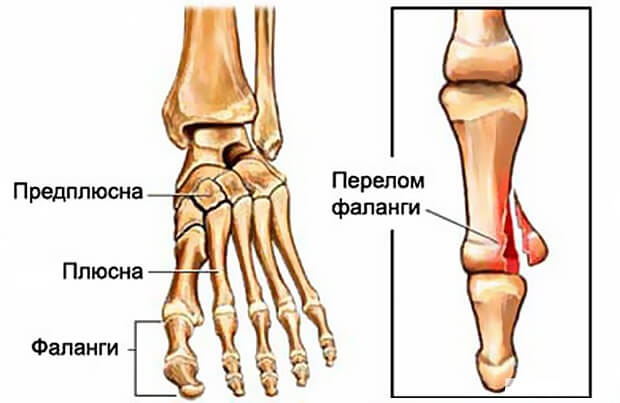

Перелом большого пальца ноги может классифицироваться по нескольким принципам:

- По типу:

- Открытый, характерен повреждением тканей и кожи, обломки кости разрывают мышцы, наружный эпителиальный покров, их видно из открытой раны;

- Закрытый, кость серьезно повреждена, мышцы, связки и кожный покров остаются целыми.

- По передвижению кости в процессе травмы:

- Со смещением;

- Перелом, в процессе которого смещения не произошло — обломанные части кости остаются в анатомически верных местах.

- По характеру глубины перелома:

- Полные — кость сломана надвое;

- Неполные — кость изломана не до конца или просто треснула.

- По наличию осколков кости:

- Осложненные осколками;

- Неосложненные образованием осколков.

- По месту локализации:

- Перелом ногтевой фаланги;

- Перелом фаланги;

- Внутрисуставной.

Чаще подвержен различным видам травм большой палец стопы, в процессе движения он поддерживает вес человека, выступает вперед относительно стопы и испытывает большую нагрузку, чем остальные пальцы.